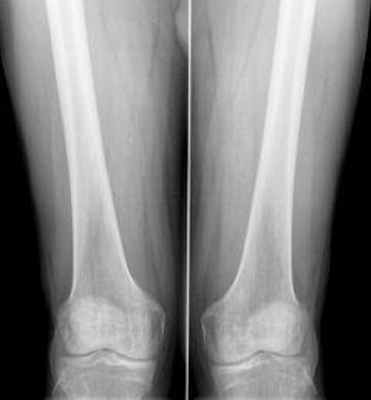

Большая берцовая кость — Кость Большеберцовая (Tibia) крупная, расположенная медиально кость голени. Её верхний эпифиз сочленяется с бедренной костью, образуя коленный сустав, нижний с таранной костью. Большеберцовая кость соединяется с малоберцовой межберцовым суставом … Википедия

Знакомство со строением бедренной кости

Исходя из анатомии бедренной кости, следует заключить, что это образование, представленное костяной тканью трубчатого типа. Ее тело имеет форму цилиндра, слегка изогнутого в передней части; вдоль его поверхности сзади идет шероховатая полоса (linea aspera), служащая местом прикрепления мышц и сухожилий. В нижней части тело начинает расширяться.

Анатомическое описание

Анатомию бедренной кости мы начнем рассматривать с проксимального эпифиза. На его поверхности располагается головка данной кости (caput femoris) с находящейся на ней суставной поверхностью, которая сочленяется с вертлужной впадиной. В центральной части поверхности на головке имеется ямочка. Соединение головки и тела кости четко выражается шейкой (Cullum femoris). Ось этого образования находится на уровне угла в сто тридцать градусов по отношению к продольной оси. Область перехода шейки в тело имеет два бугорка, называемые большим и малым вертелами. Первый выпячивается в латеральном (наружном боковом) направлении и легко обнаруживается сквозь кожу. Второй расположился сзади на внутренней части. Недалеко от большого вертела на участке бедренной шейки залегает вертельная ямка (fossa trochanterica). Вертела соединяются в передней части при помощи межвертельной линии, а вот задняя область объединяется благодаря гребню.

![седалищная кость фото]()

Анатомия бедренной кости устроена таким образом, что дистальное окончание ее тела, начиная расширяться, перетекает в латеральный и медиальный мыщелки, между которым залегает межмыщелковая ямка (fossa intercondylaris), четко выраженная сзади.

Мыщелки бедра имеют суставные поверхности, при помощи которых происходит сочленение бедренной кости с берцовой костью и надколенником. Поверхностный радиус мыщелков уменьшается от переднего к заднему направлению, формируя спираль.